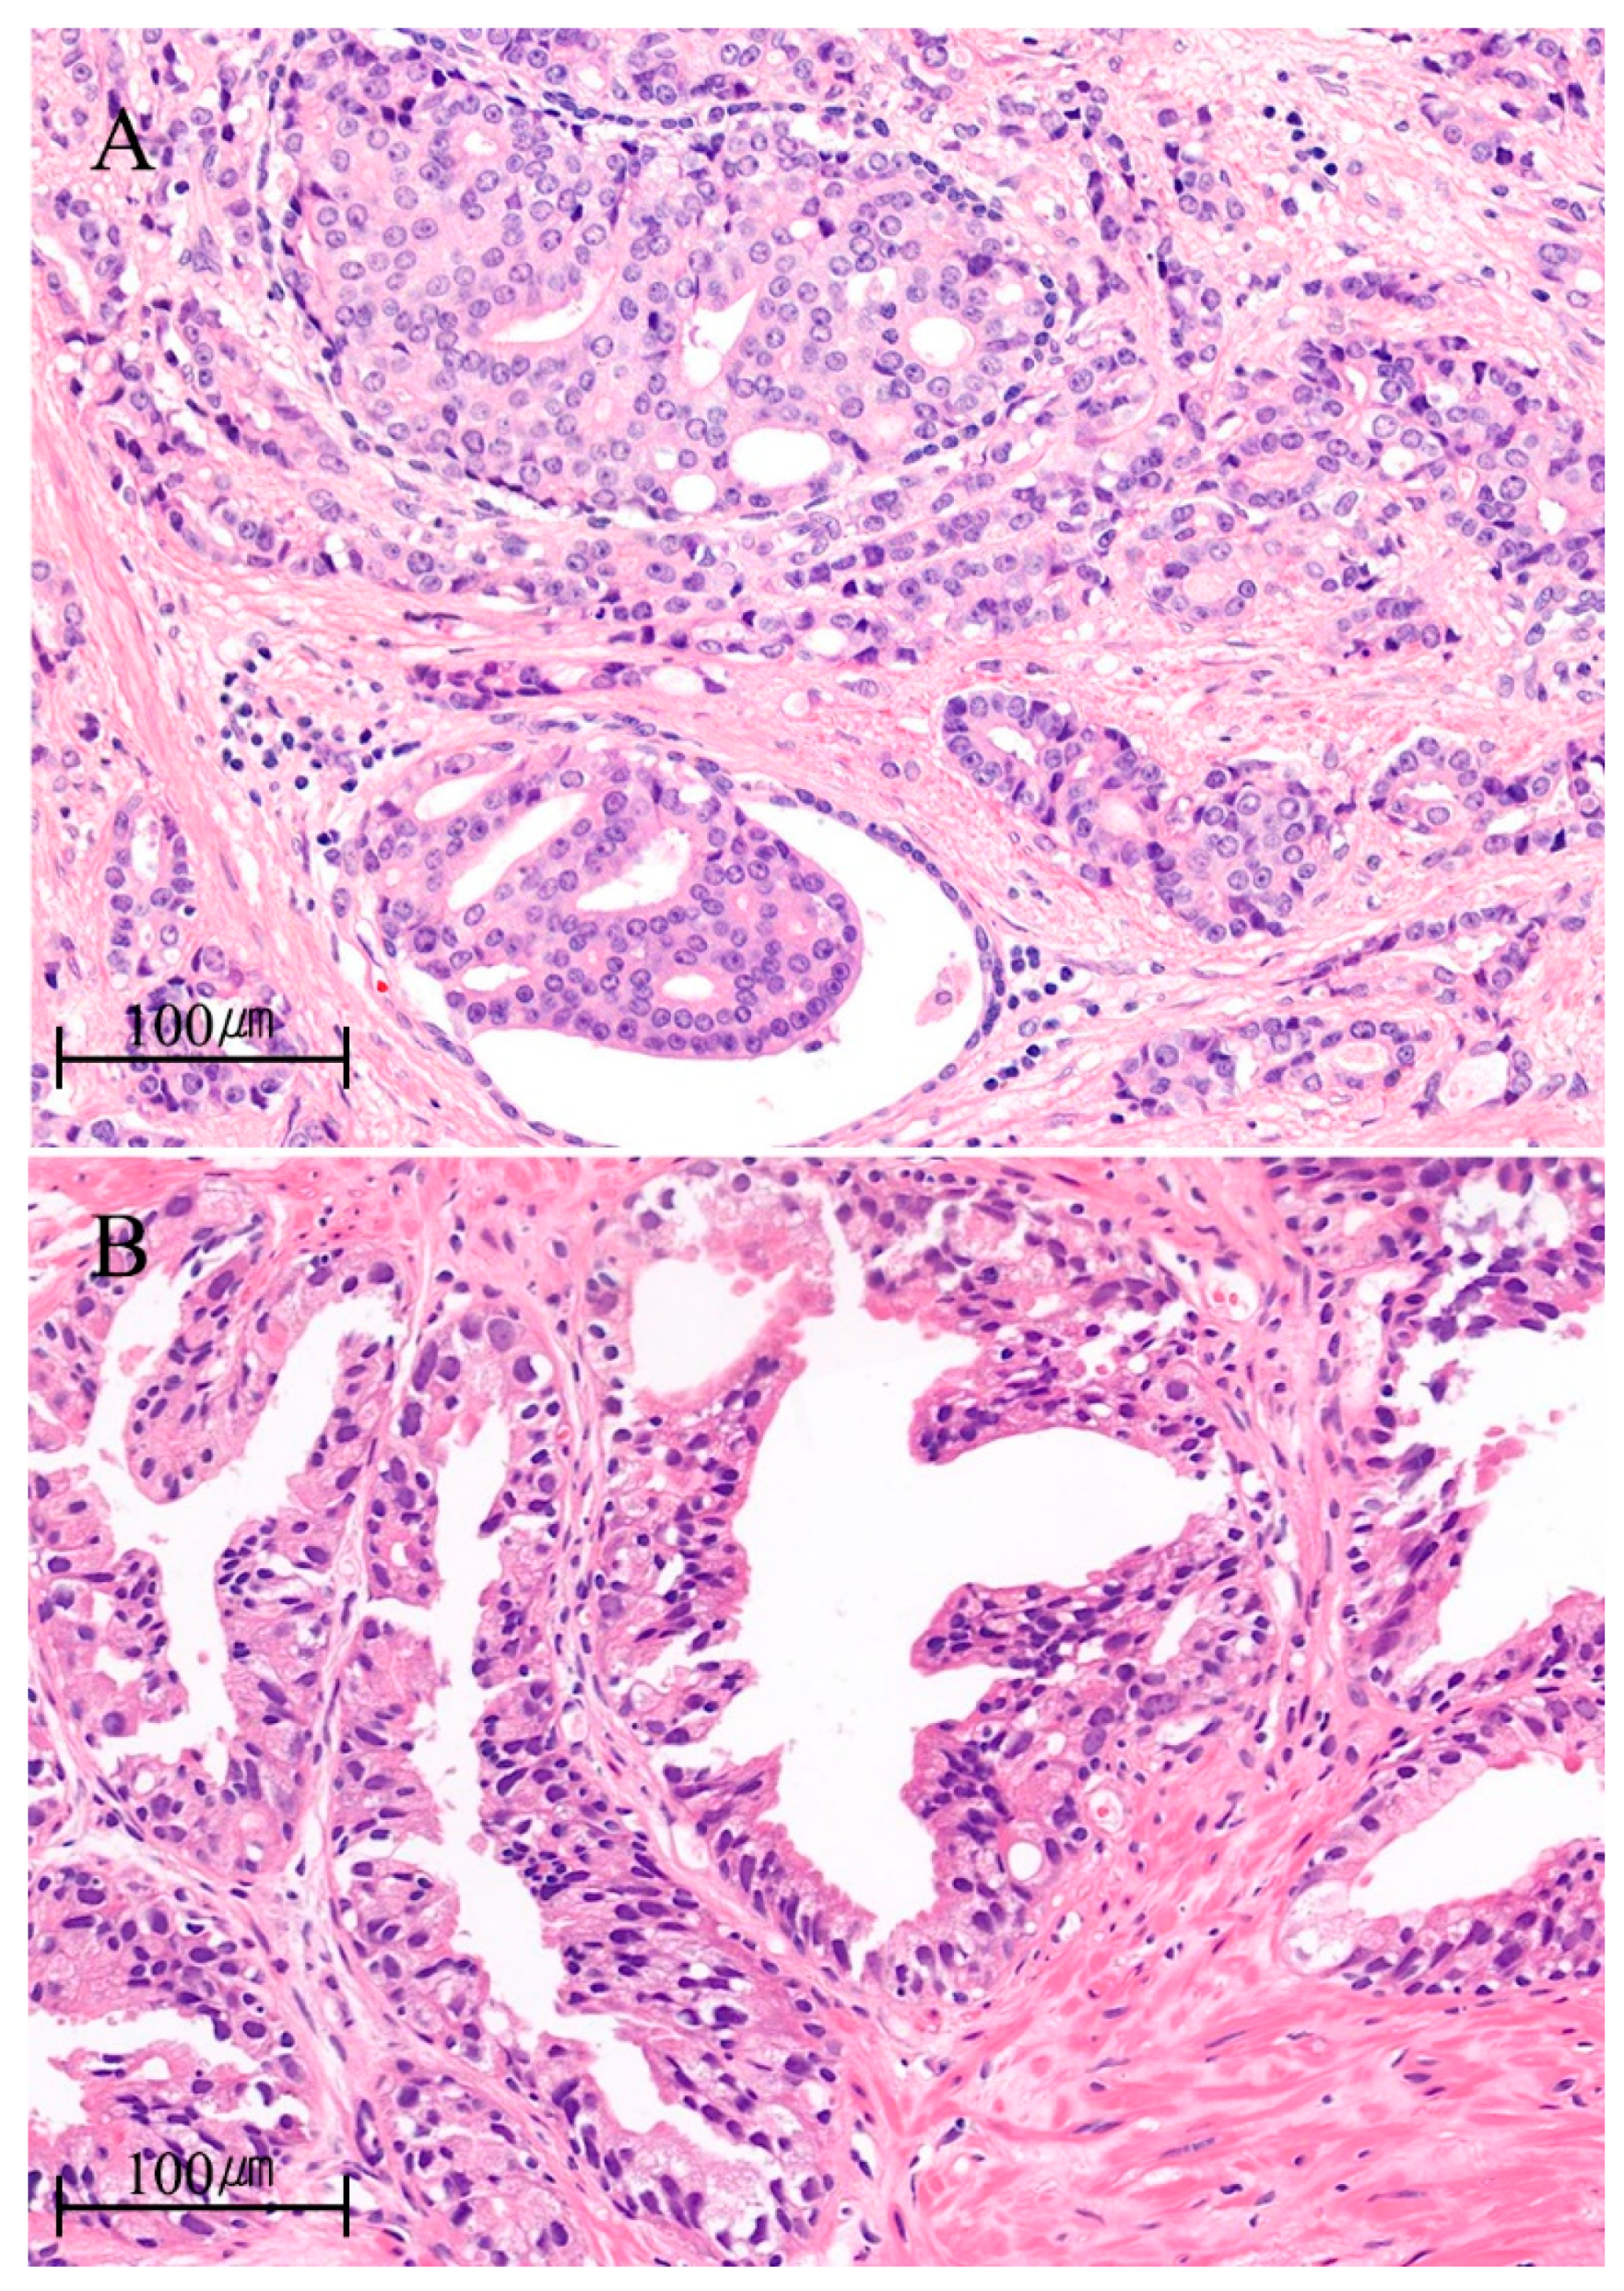

| Microscopic features [7] | • lumen-spanning, expansile growth of atypical cells |

| • solid, dense/loose cribriform, micropapillary growth pattern | |

| • cuboidal or low columnar cells | |

| • increased mitosis | |

| • marked nuclear pleomorphism | |

| • at least, partially preserved basal cell layer | |